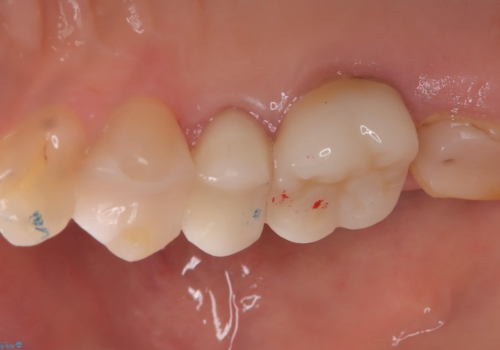

「右上4番目と5番目の間にフロスを通すといつも出血し、たまに臭いもする」という主訴で来院されました。

右上4番に歯冠色インレーが入っており、遠心側室エリアのマージン不適を認め、そこに汚れが溜まりやすい状態となっていました。

現在入っているインレー・CR裏層を除去し、再度CR裏層・セラミックインレー形成しました。